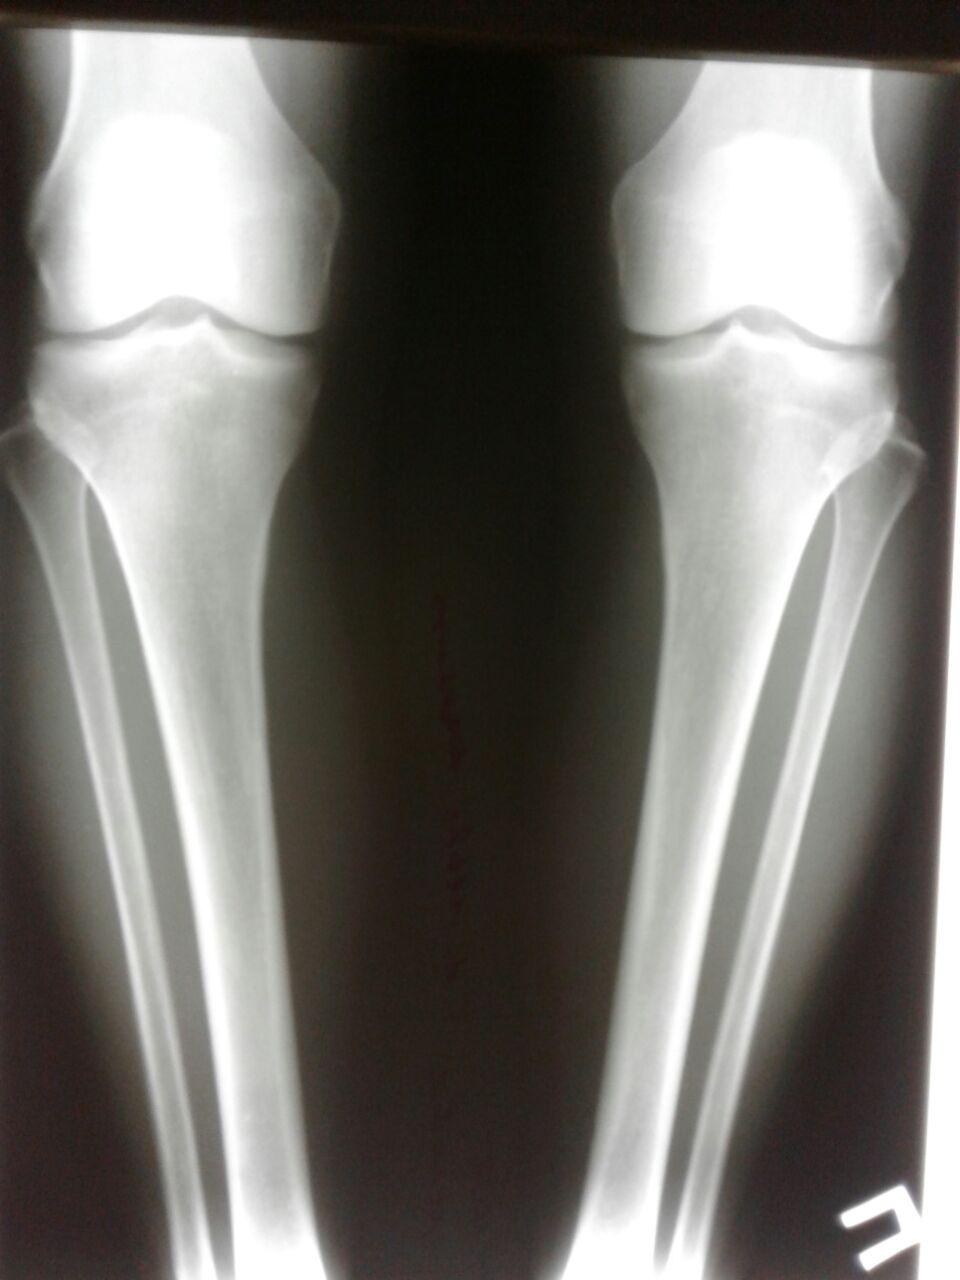

Исходник - 54 года.

Дата операции 20.10.2017г.

Дата операции 20.10.2018.

Дата снятия аппаратов 24.01.2018г.

Срок лечения 94 дня.